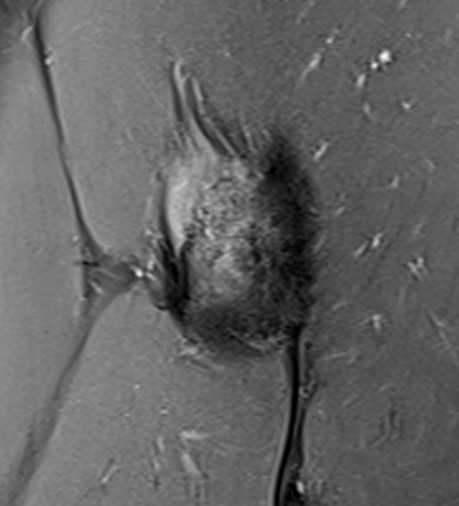

Intact gluteus medius insertion

Torn gluteus medius and minimus

Acute tear gluteus medius